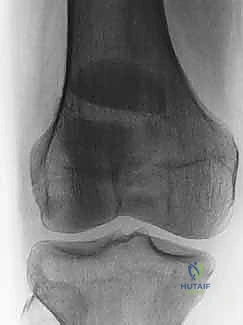

الأشعة السينية (X-rays): هي الخطوة الأولى والأساسية. يتم أخذ صور من زوايا متعددة:

- المنظر الأمامي الخلفي (AP View): لتقييم النمط العام للكسر.

- المنظر الجانبي (Lateral View): حاسم جداً لتقييم مدى تباعد أجزاء الكسر (Displacement) وعدم انتظام السطح المفصلي (Articular step-off).

- منظر السماء (Skyline View): مفيد لرؤية الكسور الطولية وتقييم التمفصل بين الرضفة وعظم الفخذ، ويتم إجراؤه إذا كانت حالة المريض تسمح بثني الركبة قليلاً.